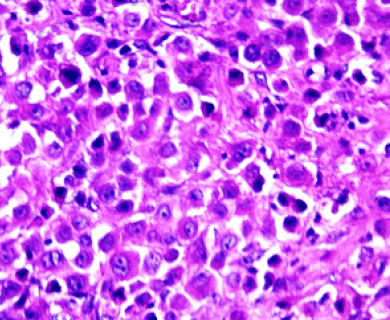

Pathologists look at tumor and tissue samples and determine what cells they can see. If the majority of cells from your mesothelioma sample are epithelioid cells, your mesothelioma subtype is determined to be epithelioid mesothelioma.

A tissue biopsy is the only way to diagnose epithelioid mesothelioma. This procedure involves taking samples of suspicious tissue. Pathologists examine the tissue samples under a microscope to identify specific cell characteristics.

Epithelioid mesothelioma cells clump together in groups and don’t tend to travel. These cell types are less likely to spread to other areas of the body. When a pathologist confirms the presence of specific cancer cells, an accurate diagnosis of your mesothelioma type can be made.

Epithelial subtype mesothelioma describes the type of cells the pathologist is seeing under the microscope when they look at a patient’s tumor.

While epithelioid is a subtype of mesothelioma, there are further subtypes of the epithelioid type. Pathologists can identify these cell subtypes with immunohistochemistry.

Epithelioid mesothelioma has a better prognosis than other subtypes, but some epithelioid cell subtypes also have better prognoses than others. For example, adenomatoid cells are associated with a better mesothelioma survival rate.